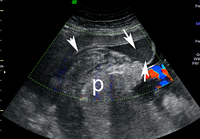

Descolamento da placenta

Imagem de ultrassonografia de descolamento da placenta: a placenta normal está marcada com 'p'; área de descolamento indicada por setas brancas

Do acervo de Dr Y Oyelese; usado com permissão